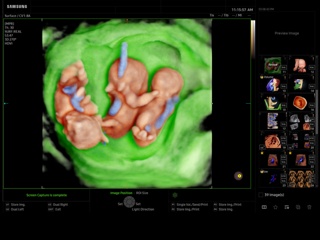

Atlas of ultrasound images - obsterics

In the section "Оbsterics" of atlas the results of ultrasonic examinations of pregnant women with different durations of gestation are represented. Here you can see images of internally organs, cerebrum, cordis and the sex of the fetus, the sonograms of multiple pregnancy, the blood flow in placenta and umbilical cord, defects of fetal`s development, etc.